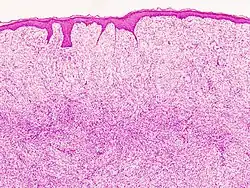

Mikroskopowo guz jest słabo odgraniczony, zajmuje skórę właściwą i nacieka do tkanki podskórnej. Zwykle nie obserwuje się nacieku naskórka, możliwe jest występowanie strefy Grenza (objaw strefy granicznej) polegającym na występowaniu pomiędzy naciekiem a naskórkiem niezmienionej powierzchniowej warstwy brodawkowatej skóry właściwej[3].

W centralnej części guz jest zbudowany z jednolitych, smukłych komórek wrzecionowatych ułożonych wirowato lub promieniście[18][3]. Komórki zawierają skąpą ilość cytoplazmy, jądro komórkowe jest wydłużone, a granice komórki są niewyraźne[6]. Około 85–90% włókniakomięsaków guzowatych skóry jest nowotworem o niskim stopniu złośliwości, ale około 5% z nich z komponentą fibrosarkomatyczną wykazuje wysoki stopień złośliwości[13]. Komórki wykazują łagodną atypię, niewielki pleomorfizm jądrowy i łagodną do umiarkowanej aktywność mitotyczną[3][18]. Zrąb jest stosunkowo ubogi, liczba naczyń jest niewielka[6]. Większość guzów jest bogatokomórkowa, ale mogą występować obszary ubogokomórkowe odpowiadające zwyrodnieniu śluzowatemu[18]. Warstwy powierzchowne guza, gdzie dochodzi do nacieku sąsiednich struktur, są mniej komórkowe i komórki wrzecionowate są pooddzielane pasmami kolagenu[3][7].